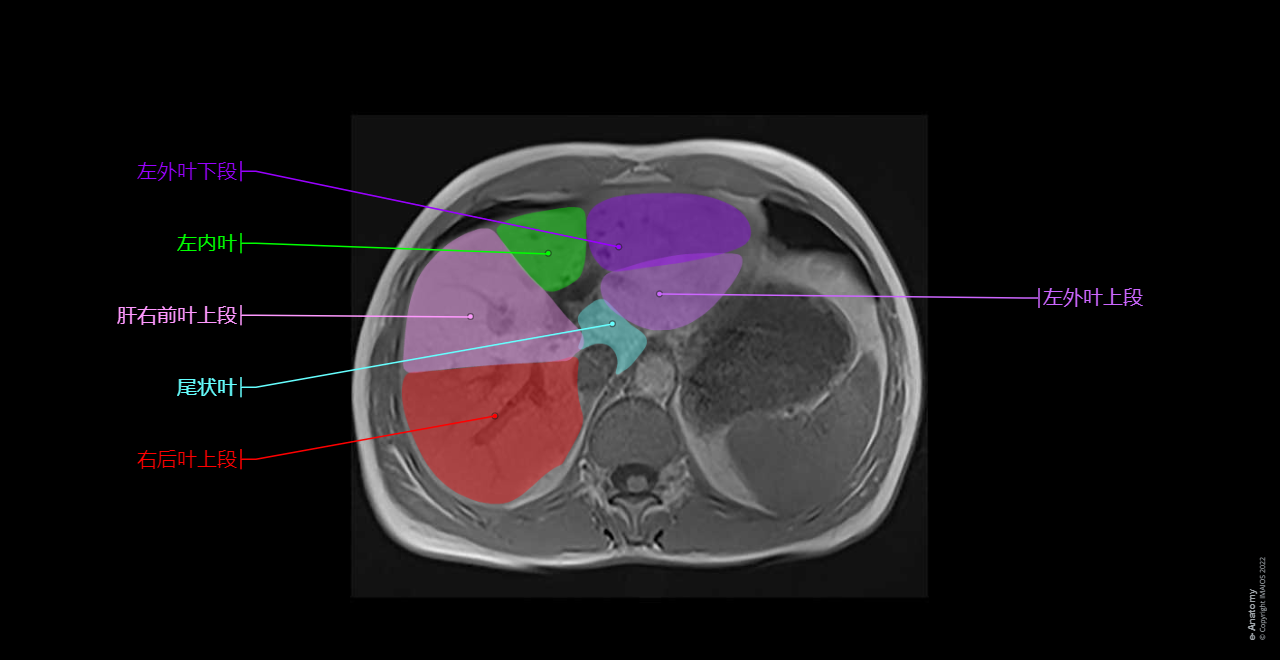

This anatomical module of e-Anatomy is dedicated to the anatomy of the biliary tract on MRI on a MRCP (magnetic resonance cholangiopancreatography).

To emphasize our pedagogic goal in anatomy, we did not choose a healthy patient where the thin (not dilated) biliary tree may have been difficult to see on MRI, but a patient with dilated biliary tree (intrahepatic ducts and common bile duct) on a choledocholithiasis (gallstone) of the distal common bile duct.

Note that in the case displayed in this module, the patient presents a small anatomical variation of the biliary tree anatomy, type IIIA (the right posterior hepatic duct draining into the left hepatic duct (see diagram below)).

Axial T1 in-phase and axial T1 out-of-phase on the liver: Conventional abdominal MRI imaging to study extraductal structures (hepatic segments, pancreas, spleen, kidneys)